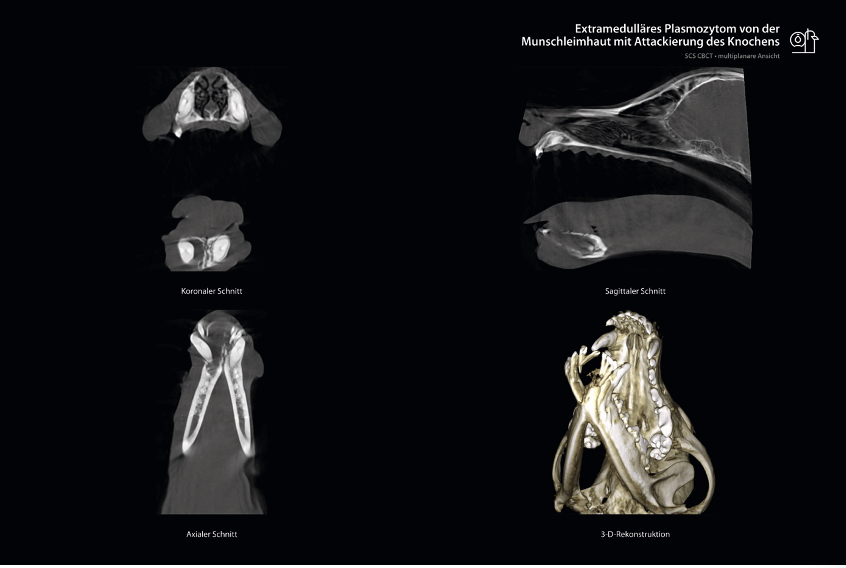

Ein 8-jähriger, männlich-kastrierter Mischlingsrüde wurde mit dem Vorbericht einer Schwellung lingual am Eckzahn im Unterkiefer vorgestellt. Im geschlossenen Zustand des Maules war diese für den Besitzer nur schwer zu erkennen. Eine Schmerzhaftigkeit oder andere Symptome zeigte der Patient bisher nicht. Es stand schnell der Verdacht auf ein tumoröses Geschehen im Raum. Dementsprechend wurde eine Untersuchung mit der CBCT-Bildgebung durchgeführt. Der Scan ergab ein hochgradiges Ausmaß an Knochenverlust der mesialen Anteile beider Unterkieferäste. Die involvierten Zähne wurden teilweise nur noch vom umliegenden Weichteilgewebe in Position gehalten.

Aufgrund des Ausmaßes und des Verdachts auf einen malignen Prozess wurde zuerst eine Biopsie durchgeführt. Zur vorrübergehenden Verbesserung des Allgemeinbefindens des Patienten wurden die lockeren Zähne extrahiert. Das Ergebnis der Biopsie, ein extramedulläres Plasmozytom, bestätigte den Verdacht auf einen malignen Prozess. Es handelte sich um einen aggressiv wachsenden Tumor, der invasives Verhalten zeigte und unterliegendes Knochengewebe zerstörte. Die empfohlene Therapiemethode dieses Tumors ist eine vollständige chirurgische Exzision und langfristige Kontrolle. Eine vollständige Entfernung führt nur selten zu einem Rezidiv und einer Metastasierung. Bei dem Patienten wurde in einem folgenden Eingriff eine partielle Mandibulektomie durchgeführt, um den Tumor vollständig zu entfernen. Nach einer komplikationslosen Wundheilung konnte bisher ein ungestörtes und vor allem rezidiv-freies Befinden festgestellt werden.